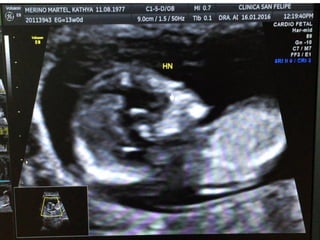

TRANSLUCENCIA NUCAL

• Personal entrenado, Ecógrafo de alta resolución

• Transabdominal, LCC:45-84mm

• Corte sagital medio. Feto en posición neutra.

• Incluyendo en la imagen sólo cabeza y tórax.

• Magnificación de la imagen(75%).

• Calipers emplazados de interno- interno de los bordes de la

TN y en sentido perpendicular.

• Diferenciar el amnios de la piel